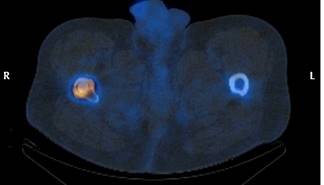

Con respecto al uso de otras pruebas empleadas en el diagnóstico por imagen del aflojamiento, cabe destacar la tomografía axial computarizada (TAC) (Figura 6) y la gammagrafía (Figura 7). Se efectuaron en 36.8% de los pacientes con aflojamiento sin fractura para confirmación diagnóstica de dicho aflojamiento, cuando éste era inconcluyente a través del estudio de radiografías simples (mostrando tendencia, pero no asociación estadísticamente significativa p = 0.062). Cabe reseñar también que no fueron empleadas para la ayuda al diagnóstico en ninguno de los pacientes del grupo de los casos.

Figura 7: Diagnóstico de aflojamiento por medio de gammagrafía. Se aprecia hipercaptación en la punta del vástago.